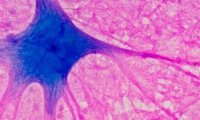

Метиленовый синий: чудо-средство для мозга или опасный эксперимент?

Метиленовый синий рекламируют как средство для улучшения памяти и работы мозга. Но так ли он безопасен? Узнайте, что говорят научные исследования о его эффективности и рисках.